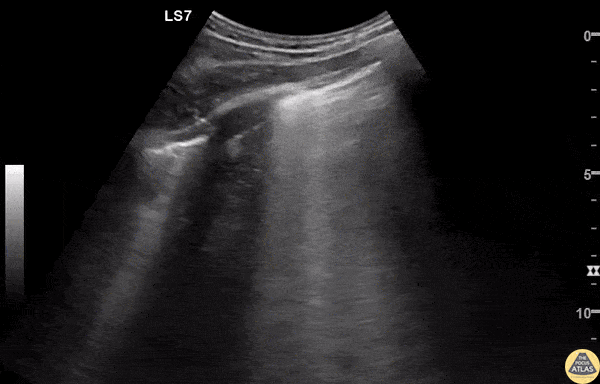

Pulmonary - B lines - Aspiration Pneumonitis

A 30s M presented to the ED after he was found down in the setting of substance use. He received naloxone from EMS with good response, but on arrival to the ED was hypoxic and in respiratory distress, requiring maximum levels of respiratory support. POCUS was performed, showing extensive confluent B lines in both lungs, though worse on the right, suggestive of the alveolar interstitial syndrome and concerning for aspiration pneumonitis. The patient required intubation for work of breathing, and was admitted for further management. Dr. James Sutton, PGY2 Denver Health Residency in Emergency Medicine